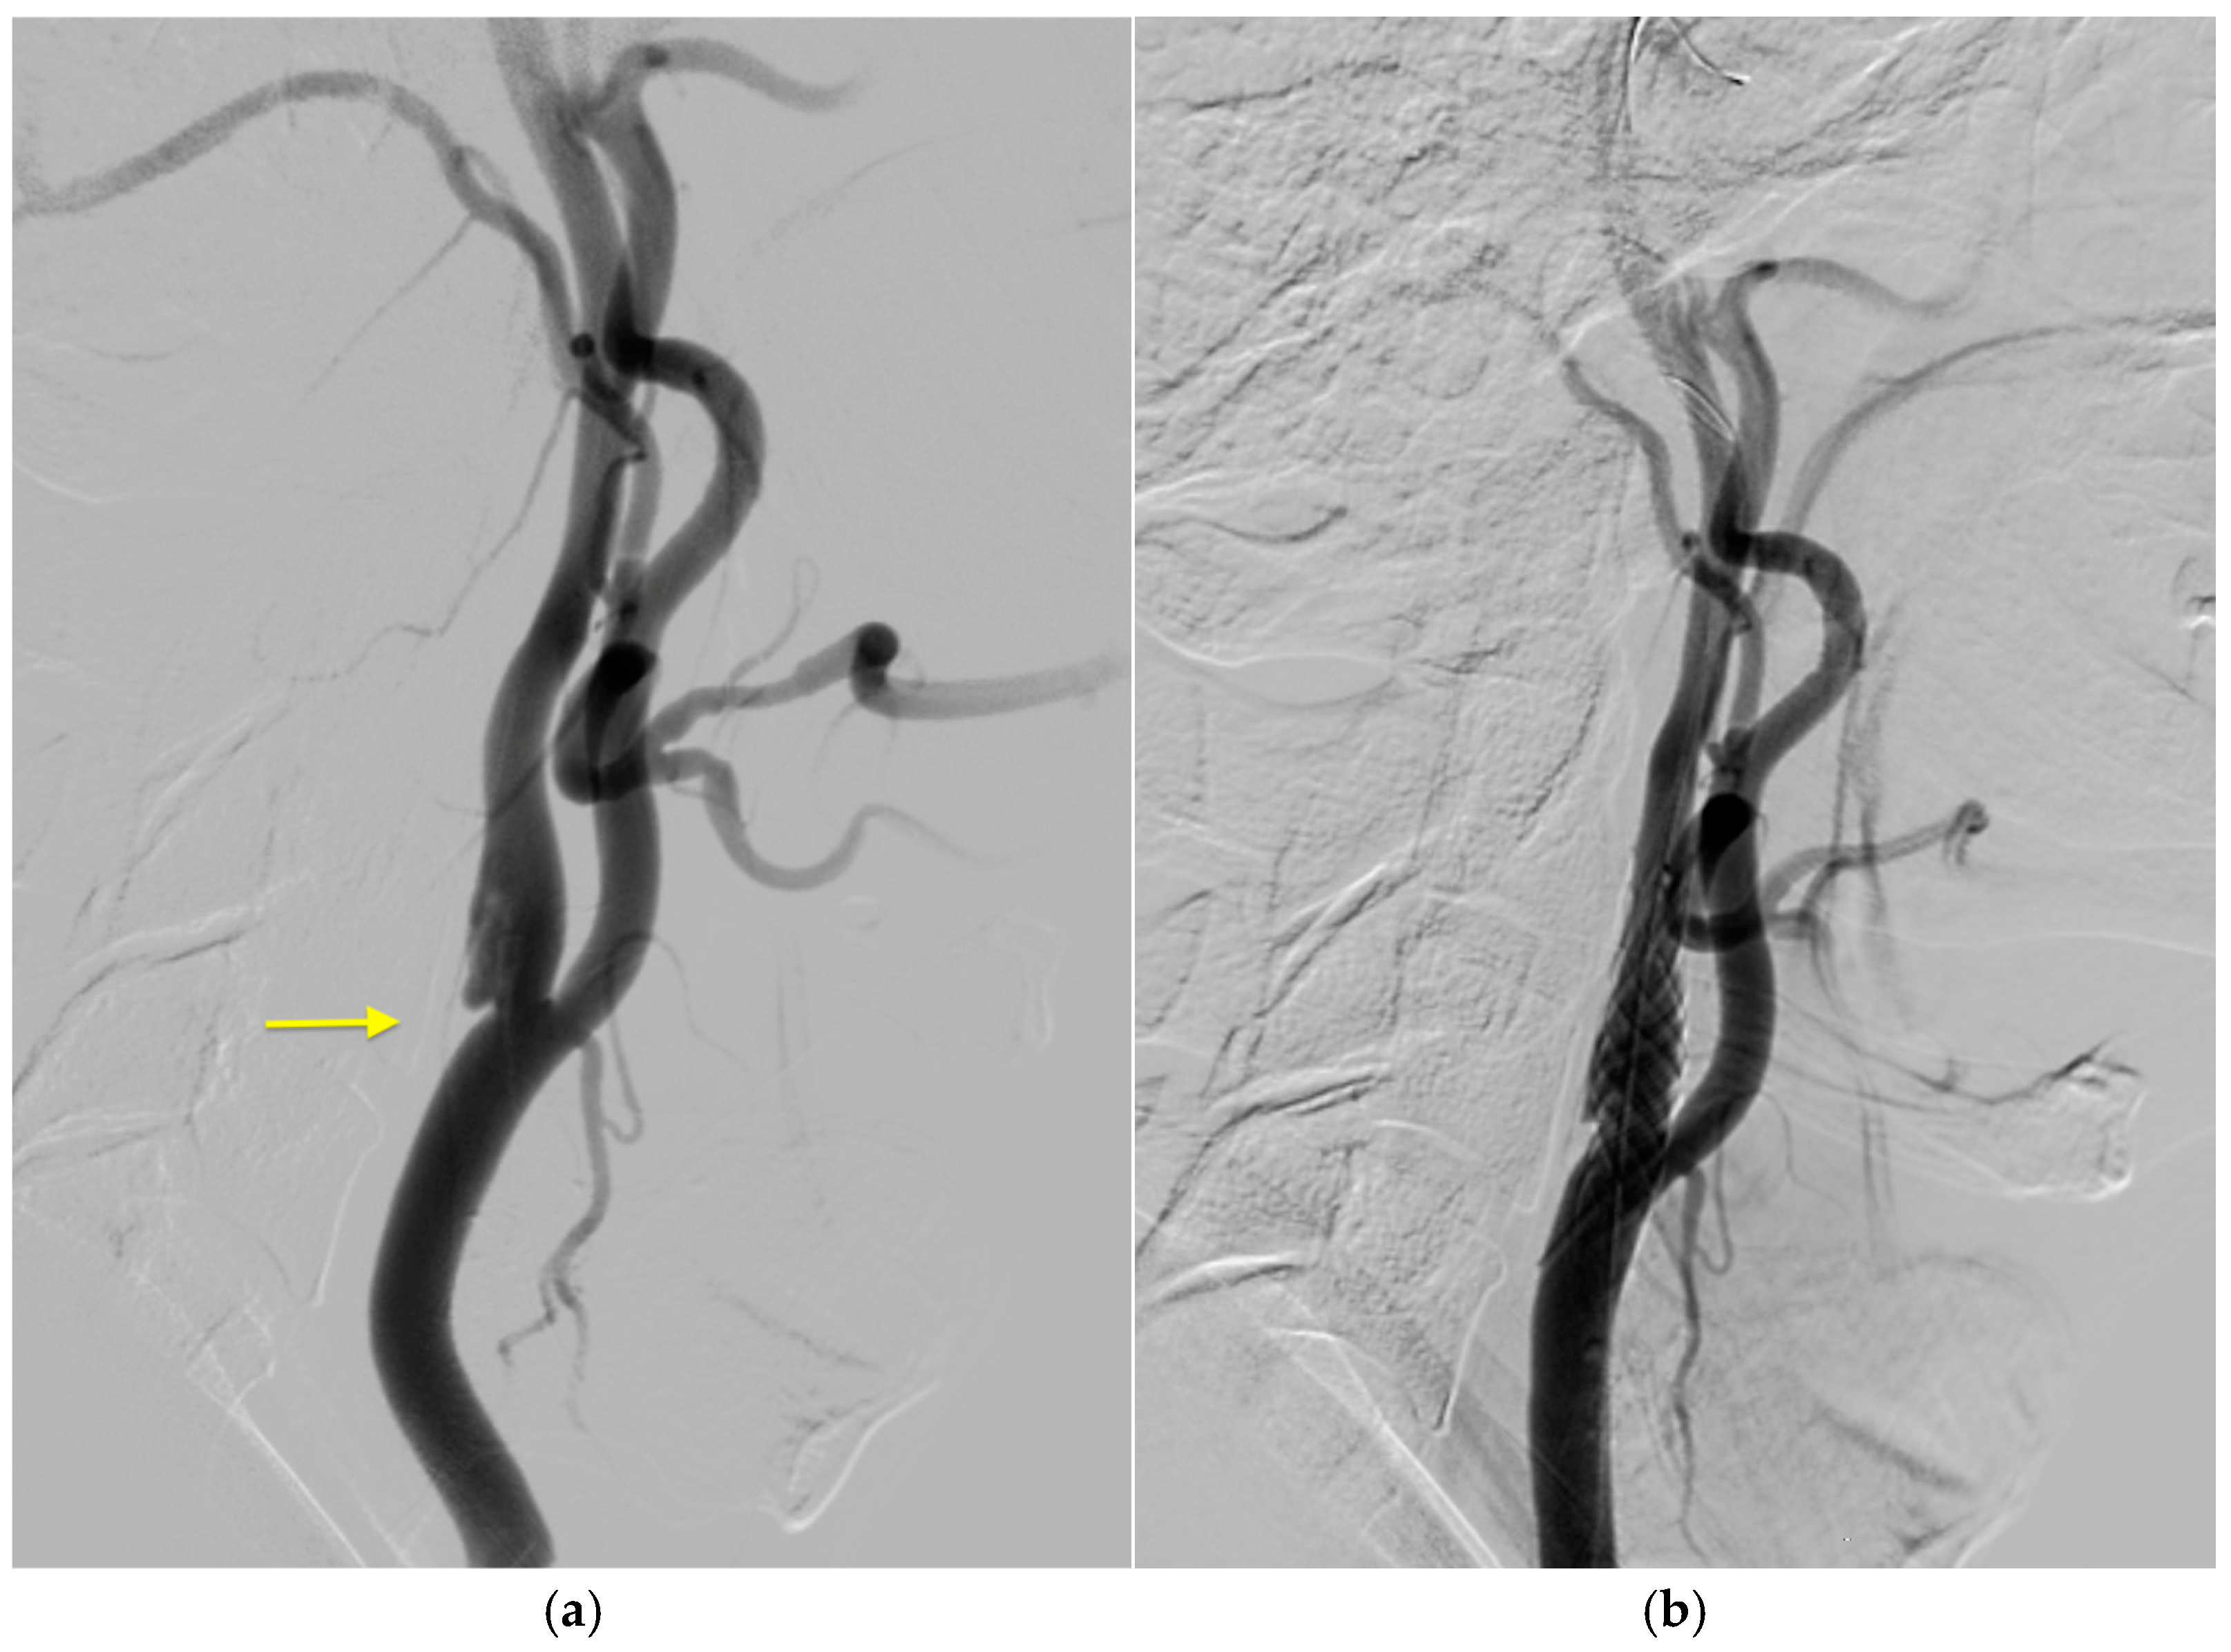

2. Case History